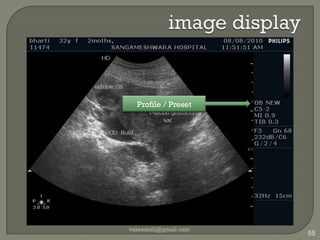

image displayvaseemali@gmail.com55Profile / Preset